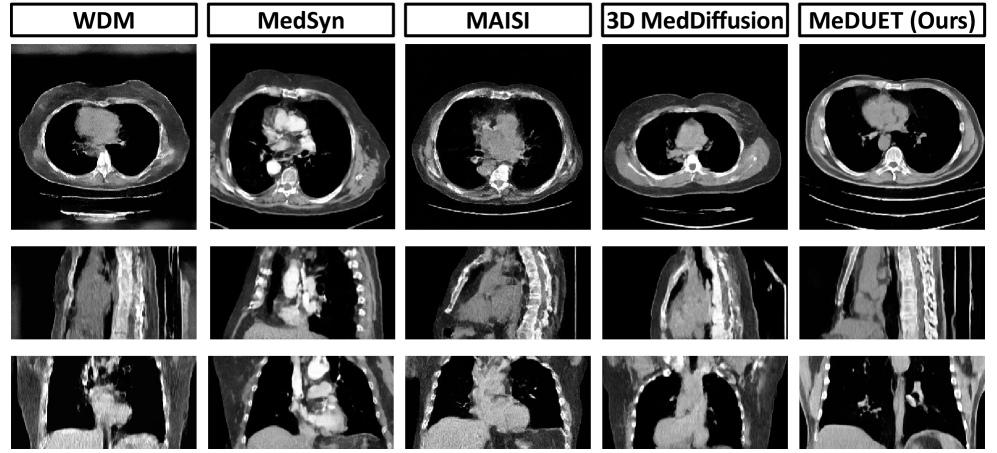

Refer to caption

Figure 4: Qualitative comparison of synthesized volumes.

Synthesis Quality Comparison. We exclude any improvements to DiT and SiT, such as architectural modifications [20, 94] and acceleration techniques [89, 87], which are not line with our core objective. From Table 1, MeDUET achieves SOTA performance across all three metrics, with FID scores of 0.7874 and 0.8611 for SiT and DiT, respectively, and achieves lower MMD and MS-SSIM values than all baselines, indicating superior anatomical fidelity and appearance diversity. The learned disentangled factors consistently outperform the previously used metadata vectors, emphasizing the effectiveness of our disentangled factor learning. Fig. 4 presents a visual comparison of images synthesized by our method and baselines.